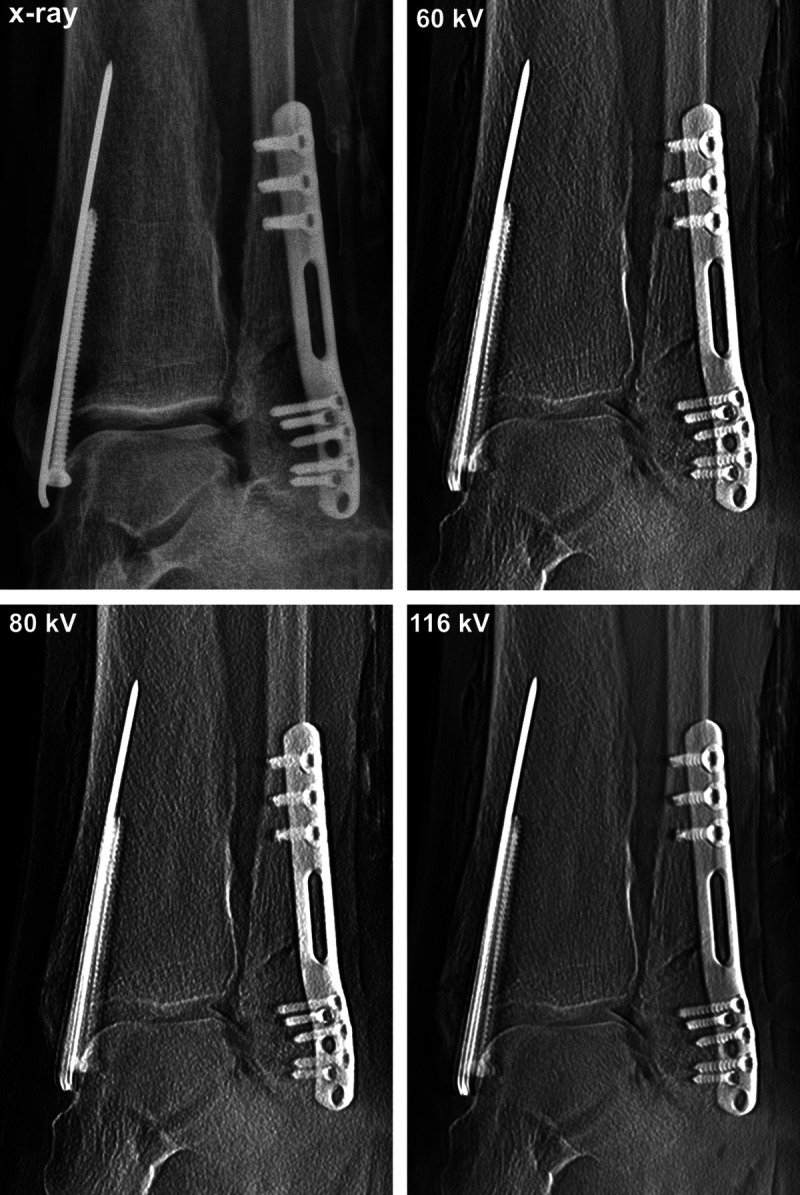

Materials and methods: After surgical fracture induction and subsequent osteosynthesis, 8 cadaveric fracture models (wrist, metacarpus, ankle, metatarsus) were scanned with the prototypical tomosynthesis mode of a multiuse x-ray system. Tomosynthesis protocols at 60, 80, and 116 kV (sweep angle 10°, 13 FPS) were compared with standard radiograms. Five radiologists independently rated diagnostic assessability based on an equidistant 7-point scale focusing on fracture delineation, intra-articular screw placement, and implant positioning. The intraclass correlation coefficient (ICC) was calculated to analyze interrater agreement.

Results: Radiation dose in radiography was 0.48 ± 0.26 dGy·cm 2 versus 0.12 ± 0.01, 0.36 ± 0.02, and 1.95 ± 0.11 dGy·cm 2 for tomosynthesis scans at 60, 80, and 116 kV. Delineation of fracture lines was superior for 80/116 kV tomosynthesis compared with radiograms ( P ≤ 0.003). Assessability of intra-articular screw placement was deemed favorable for all tomosynthesis protocols ( P ≤ 0.004), whereas superiority for evaluation of implant positioning could not be ascertained (all P 's ≥ 0.599). Diagnostic confidence was higher for 80/116 kV tomosynthesis versus radiograms and 60 kV tomosynthesis ( P ≤ 0.002). Interrater agreement was good for fracture delineation (ICC, 0.803; 95% confidence interval [CI], 0.598-0.904), intra-articular screw placement (ICC, 0.802; 95% CI, 0.599-0.903), implant positioning (ICC, 0.855; 95% CI, 0.729-0.926), and diagnostic confidence (ICC, 0.842; 95% CI, 0.556-0.934).

Conclusions: In the postoperative workup of extremity fractures, tomosynthesis allows for superior assessment of fracture lines and intra-articular screw positioning with greater diagnostic confidence at radiation doses comparable to conventional radiograms.

Abstract Image